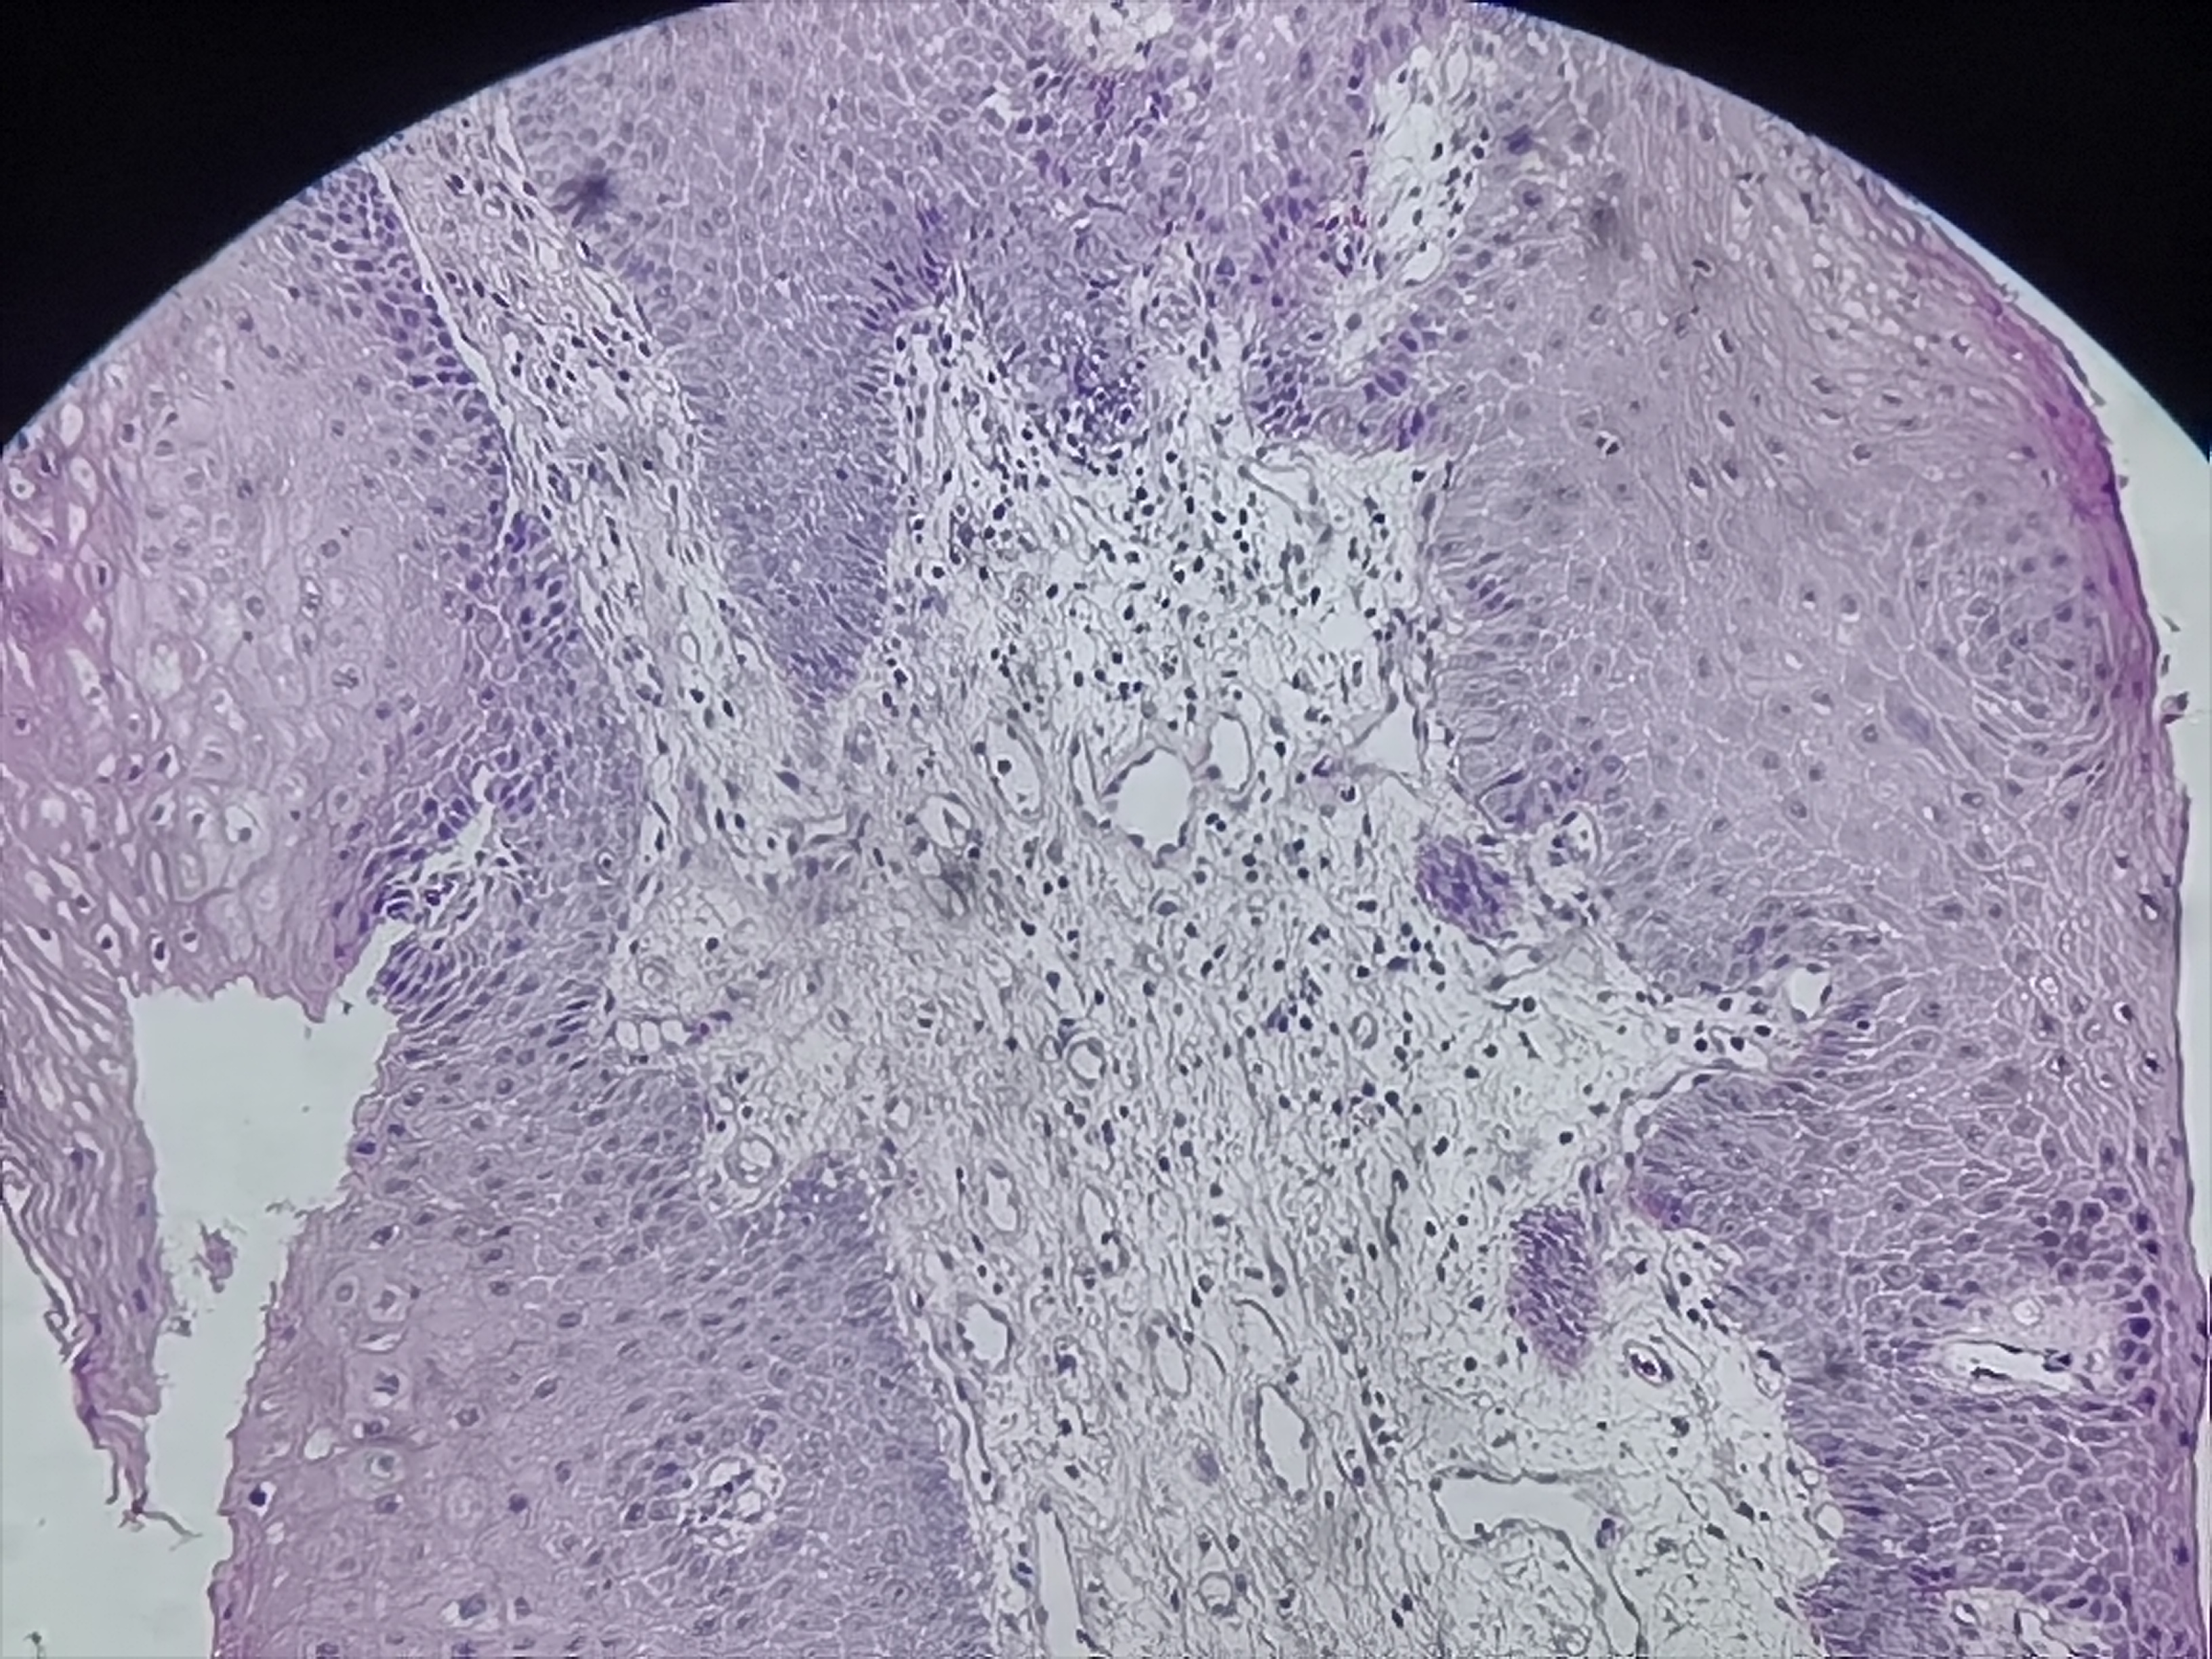

食管活检

性别

男

年龄

61岁

临床诊断

食管癌

一般病史

食管距门齿20cm处可见不规则病灶,质脆,易出血,管腔狭窄,镜子不能通过

标本名称

食管粘膜活检

大体所见

灰白色组织3块

考虑符合:鳞癌